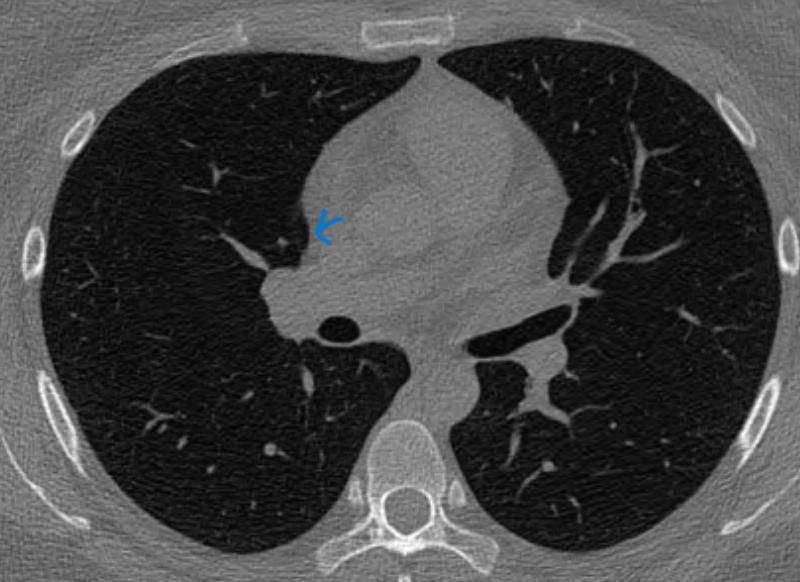

폐결절 간유리인가요 반고형 간유리인가요, 고형인가요

첫병원은 어느슬라이드에서는 고형같기도하지만 간유리같다.지금 큰병원은 처음엔 간유리랫는데 영상의학과 판독후 고형이라고 나온후 두번째 병원도 갑자기 고형이래요.

슬라이드 하나넘길때마다 아주옅은 간유리에서 음영짙은 결절에서 또 넘기면 완전 하얀 고형처럼 보여요.

파란색, 붉은색 화살표 표시있는게 시리즈5 1thk인데

시리즈 2인 3thk만 보면서 진료를 받은거 같아요. 파란색 사진의 고형도 안나오고,

빨간색 사진의 짙음 음영 고형?반고형?간유리 결절이 안보이는 ct영상